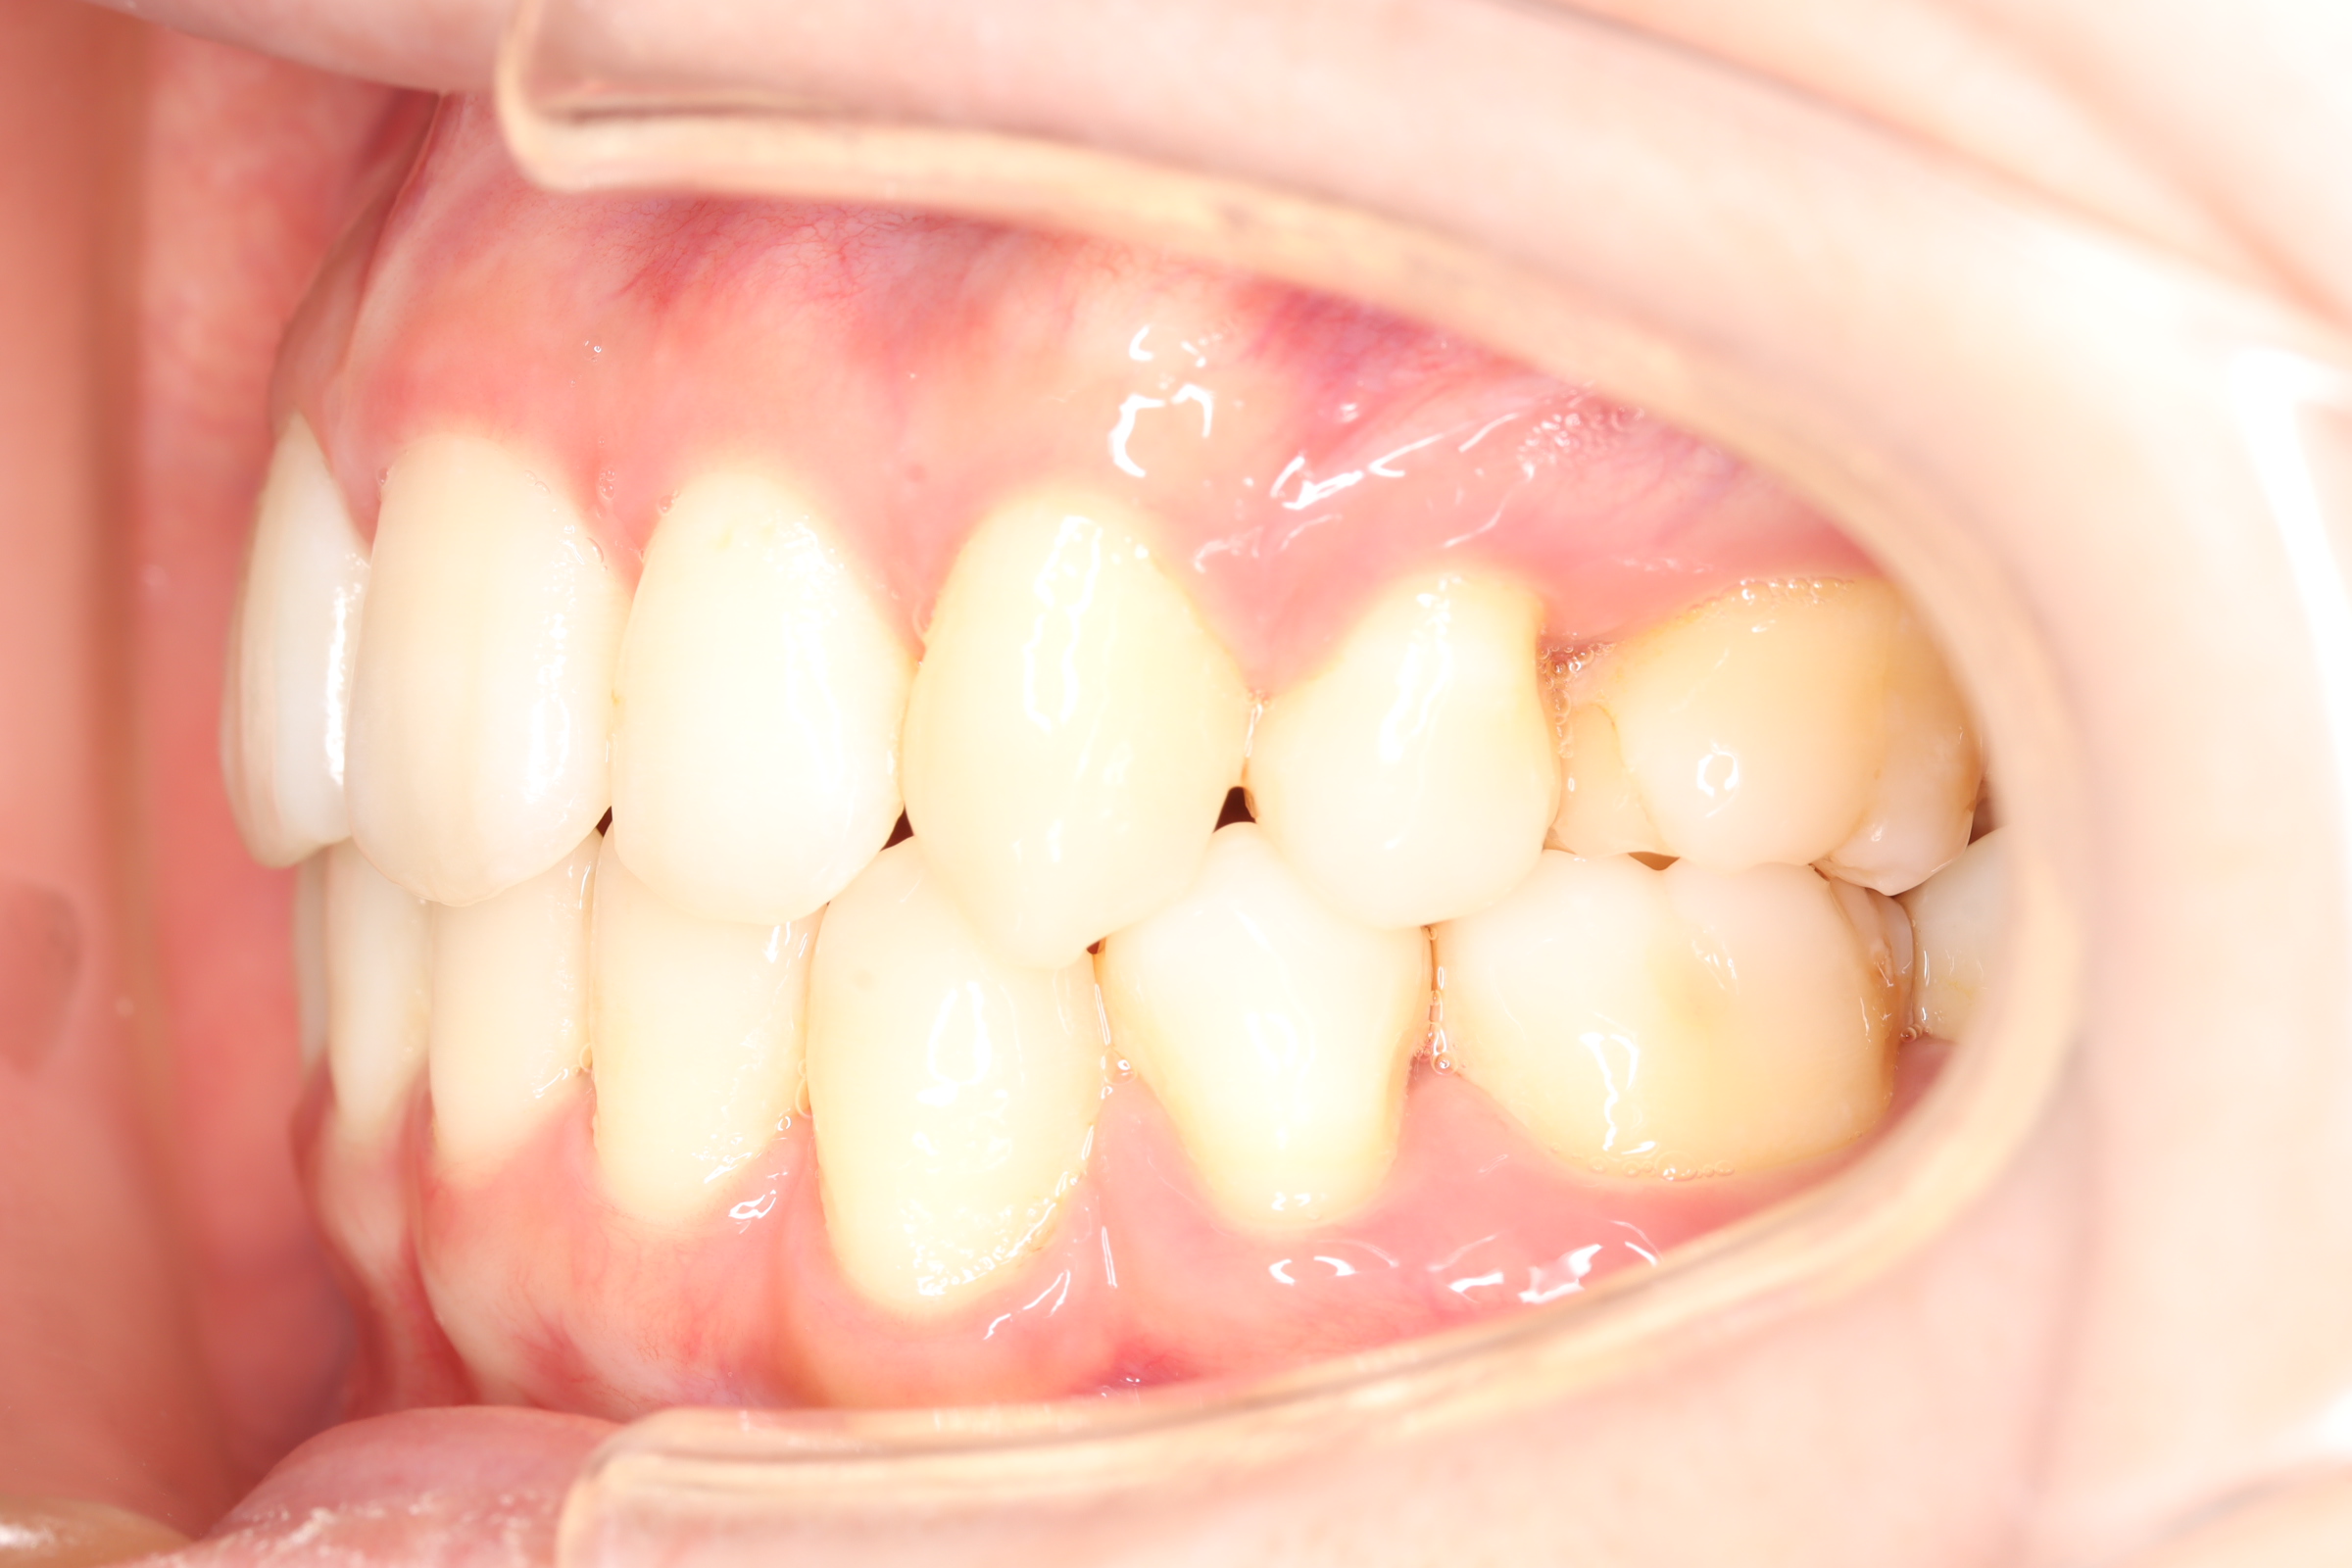

舌側(リンガル)矯正での叢生(ガチャ歯)の治療

口腔内の変化

| 治療前 | SNSなどで「ガチャ歯」と呼ばれている、見た目のがたつきを治したかった患者さんです。 骨格的な問題はありませんでしたが、上下の前歯が唇側傾斜しており、上下顎前突症で口元の突出感がありました。 |

| 治療後 | 前歯から奥歯まで全体的に緊密な咬み合わせになっています。 歯のガタつきが無くなることにより、綺麗な見た目と歯磨きのしやすい口腔内環境になりました。 また突出感のあった口元もすっきりして綺麗なEラインとなり横顔も変化しました。 しっかりとしたかみ合わせを作ることにより、綺麗な歯並びになります。 |